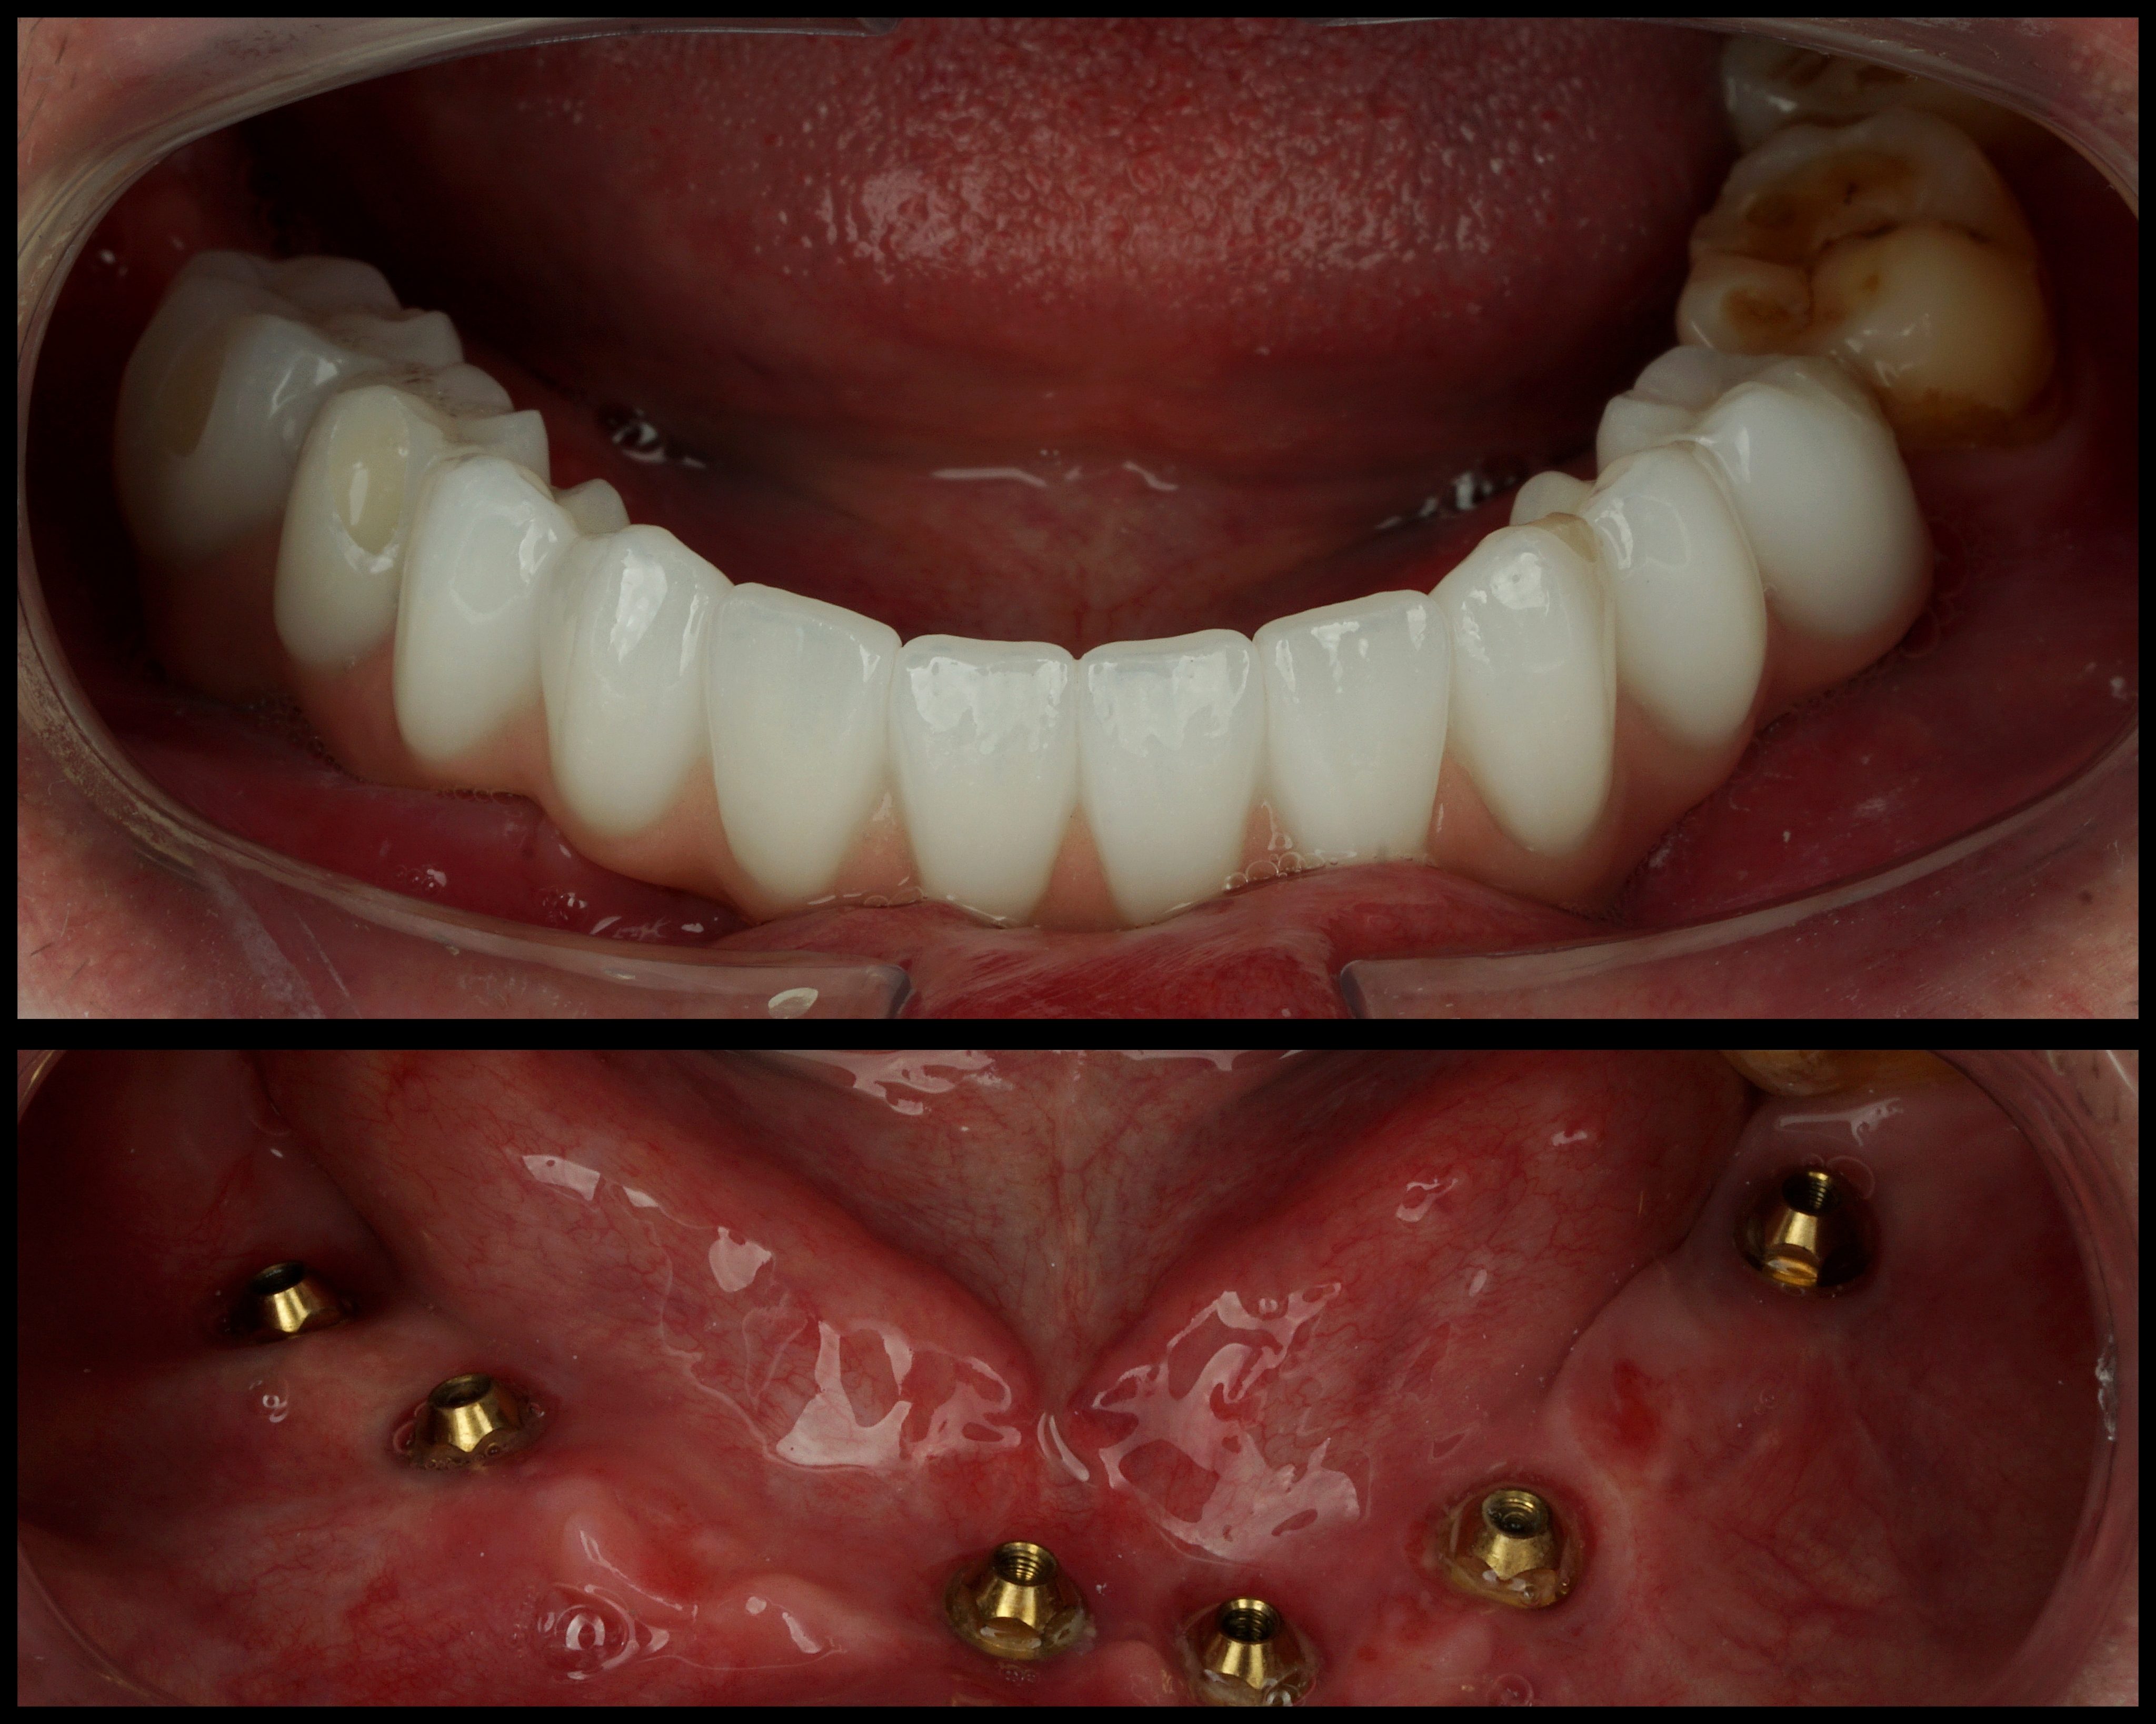

All-on-6 je moderní způsob náhrady celého zubního oblouku pomocí šesti implantátů, na kterých je upevněna fixní protetická práce.

Cílem ošetření All-on-6 je obnovit estetiku úsměvu, jistotu při kousání a komfort při každodenním fungování. Vhodnost tohoto postupu závisí na anatomii čelisti, kvalitě kosti, skusu a celkovém léčebném plánu.

Pokud jsou přítomny zuby, které již nelze dlouhodobě zachovat, může být součástí léčby jejich odstranění. Následně je podle léčebného plánu zavedeno šest implantátů, které slouží jako opora budoucí fixní náhrady.

Po implantaci následuje hojení. Za vhodných podmínek je v některých případech možné provést dočasné zatížení protetickou náhradou v krátkém čase po zákroku. Definitivní práce se zhotovuje po stabilizaci a vhojení implantátů.